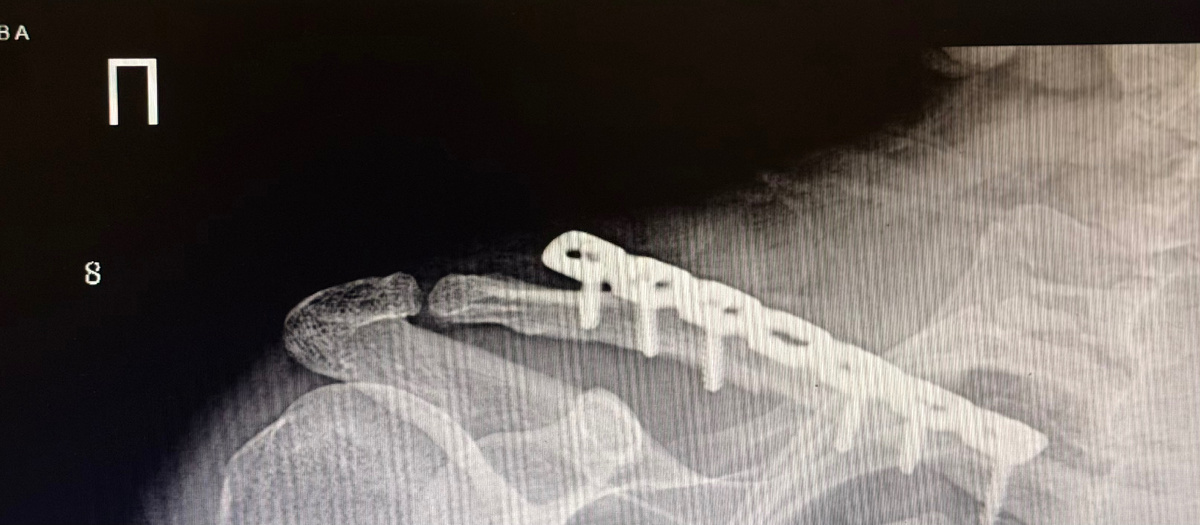

Остеосинтез ключицы - показания

🦴 Показания к остеосинтезу ключицы